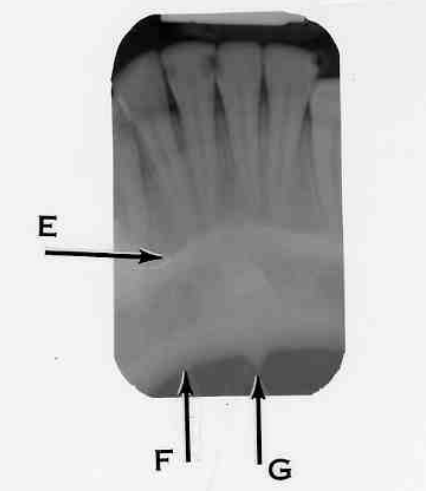

11. Which option is indicated by arrow E?

13. Arrow E showing which anatomical structure?

14. What is showing by E?

15. Arrow F showing which anatomical structure?

16. What is showing by E?